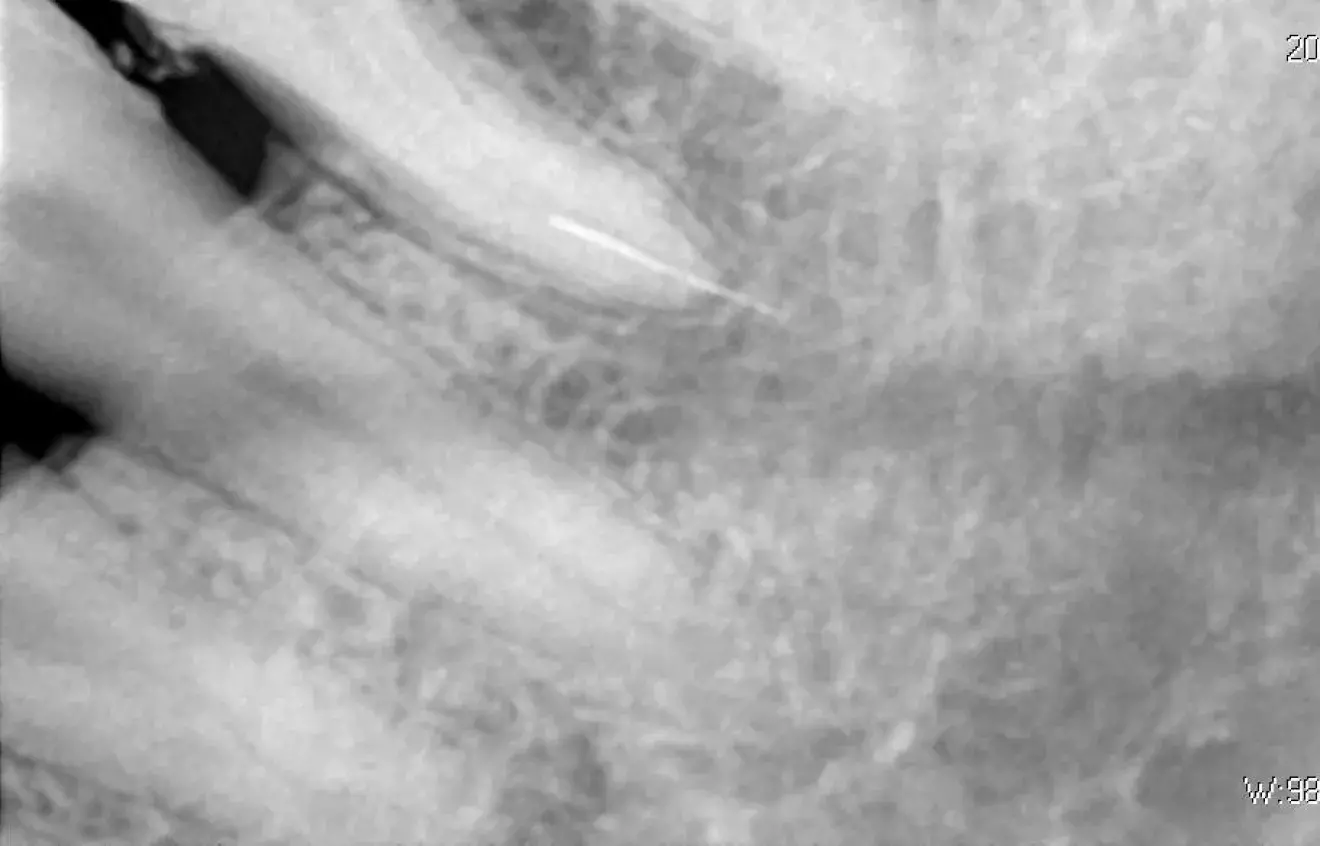

Без мікроскопа вилучити інструмент майже неможливо. Збільшення в 15-20 разів і потужне фокусоване світло дозволяють лікарю бачити кінець уламка та працювати з мікроскопічною точністю.

- Лікар обережно розширює верхню частину каналу, щоб створити прямий візуальний доступ до уламка.

- Важливо видалити мінімальну кількість дентину, зберігаючи міцність зуба.

- Ультразвук: Спеціальні мікронасадки створюють вібрацію, яка змушує уламок «викрутитися» з каналу. Часто це працює, якщо інструмент застряг у прямій частині.

- Петльові техніки (наприклад, петля Террі): За допомогою тонкого дроту або спеціального інструмента на кінець уламка накидається мікропетля, яка затягується і дозволяє витягти його.